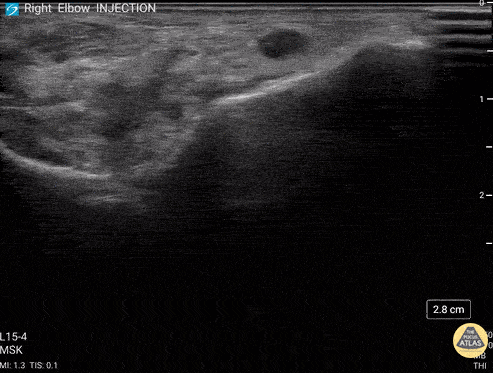

92 y/o M presented with moderate to severe osteoarthritis on elbow x-ray who was treated with ultrasound-guided corticosteroid joint injection. Video shows transverse view of the posterior elbow as corticosteroid is injected with a posterolateral approach deep to the posterior elbow fat pad located in the olecranon fossa. This area is continuous with the elbow joint capsule. Posterolateral approach is advantageous due to decreased risk of disrupting neurovascular structures or the articular cartilage from other approaches to the joint space. Posterior approach is also advantageous compared to lateral approach in moderate to severe arthritis due to limited access to the radiocapitellar joint space. Eben Alexander, DO Devesh Patel, MD Eastern Virginia Medical School